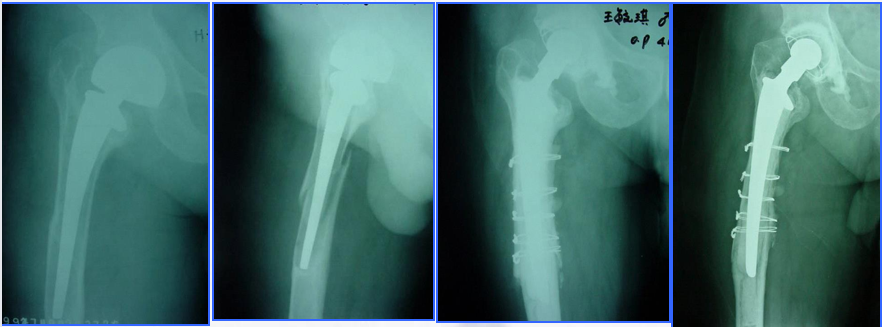

髓内固定:(二)翻修术

①适应征:假体松动的骨折

②原则:

尽可能的保留骨量

尽可能使假体与完整的宿主骨之间获得牢固固定

③假体的选择

长柄远端固定非骨水泥型

假体的长度至少要超过骨折端两倍于股骨直径的距离

骨缺损者,联合异体皮质骨板髓外固定